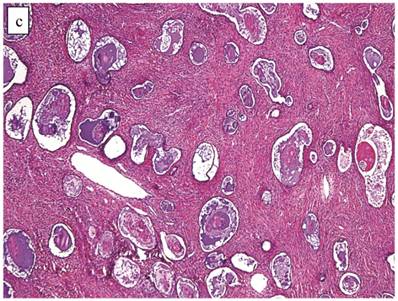

Clear Cell Carcinoma with Adenofibromatous Background (n=141)

The clinicopathologic features with respect to age, stage, bilaterality, tumor size, gross appearance, and distributions of grade and architectural pattern are shown in Table 4. Between cases, the CAs histologically displayed combinations of tubulocystic (Fig. 3A), papillary, and solid architectural patterns; hobnail, polygonal, and flat cell shapes (Fig. 3B); clear or oxyphilic cytoplasm; a spectrum of atypia ranging from mild to severe; generally low mitotic indices; and hyalinized stroma, similar to the features seen in ovarian clear cell CAs described in detail elsewhere.13,47,70,75,77

Figure 3

Carcinoma with adenofibromatous background. The carcinoma component exhibits a (A) tubulocystic pattern with (B) oxyphilic, hobnail, and flat atypical cells. (C) The adenofibromatous component does not show architectural features of clear cell carcinoma or notable atypia.

The background of the tumor contained variable amounts of adenofibromatous components (Fig. 3C). The proportion of the clear cell CA component in the tumors ranged from focal to diffuse, but cases with focal CA components exceeded conventional definitions for microinvasion (>3 mm in greatest dimension). Notable nuclear atypia was focally present in the adenofibromatous background in 34 (24%) cases, and the histologic appearance of such foci was similar to those with notable atypia in APTs described above. A comparison with non-adenofibromatous clear cell CAs is shown in Table 4.

Although the vast majority of tumors displayed overt carcinomatous growth patterns, the architecture of the entire tumor in 7 (5%) cases superficially resembled an AF/APT with fibromatous and unaltered stroma between glands; however, the combined degree of glandular crowding and variation in size and shape of the glands, haphazard arrangement of glands, substantial epithelial stratification, and diffuse marked atypia significantly exceeded the conventional appearance of AF/APT (Fig. 4). In the 6 cases with staging data, 1 (17%) had extra-ovarian disease.